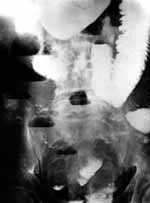

[Увеличить]

Рис. 4. Обзорная рентгенограмма брюшной полости того же больного после перорального контрастирования.